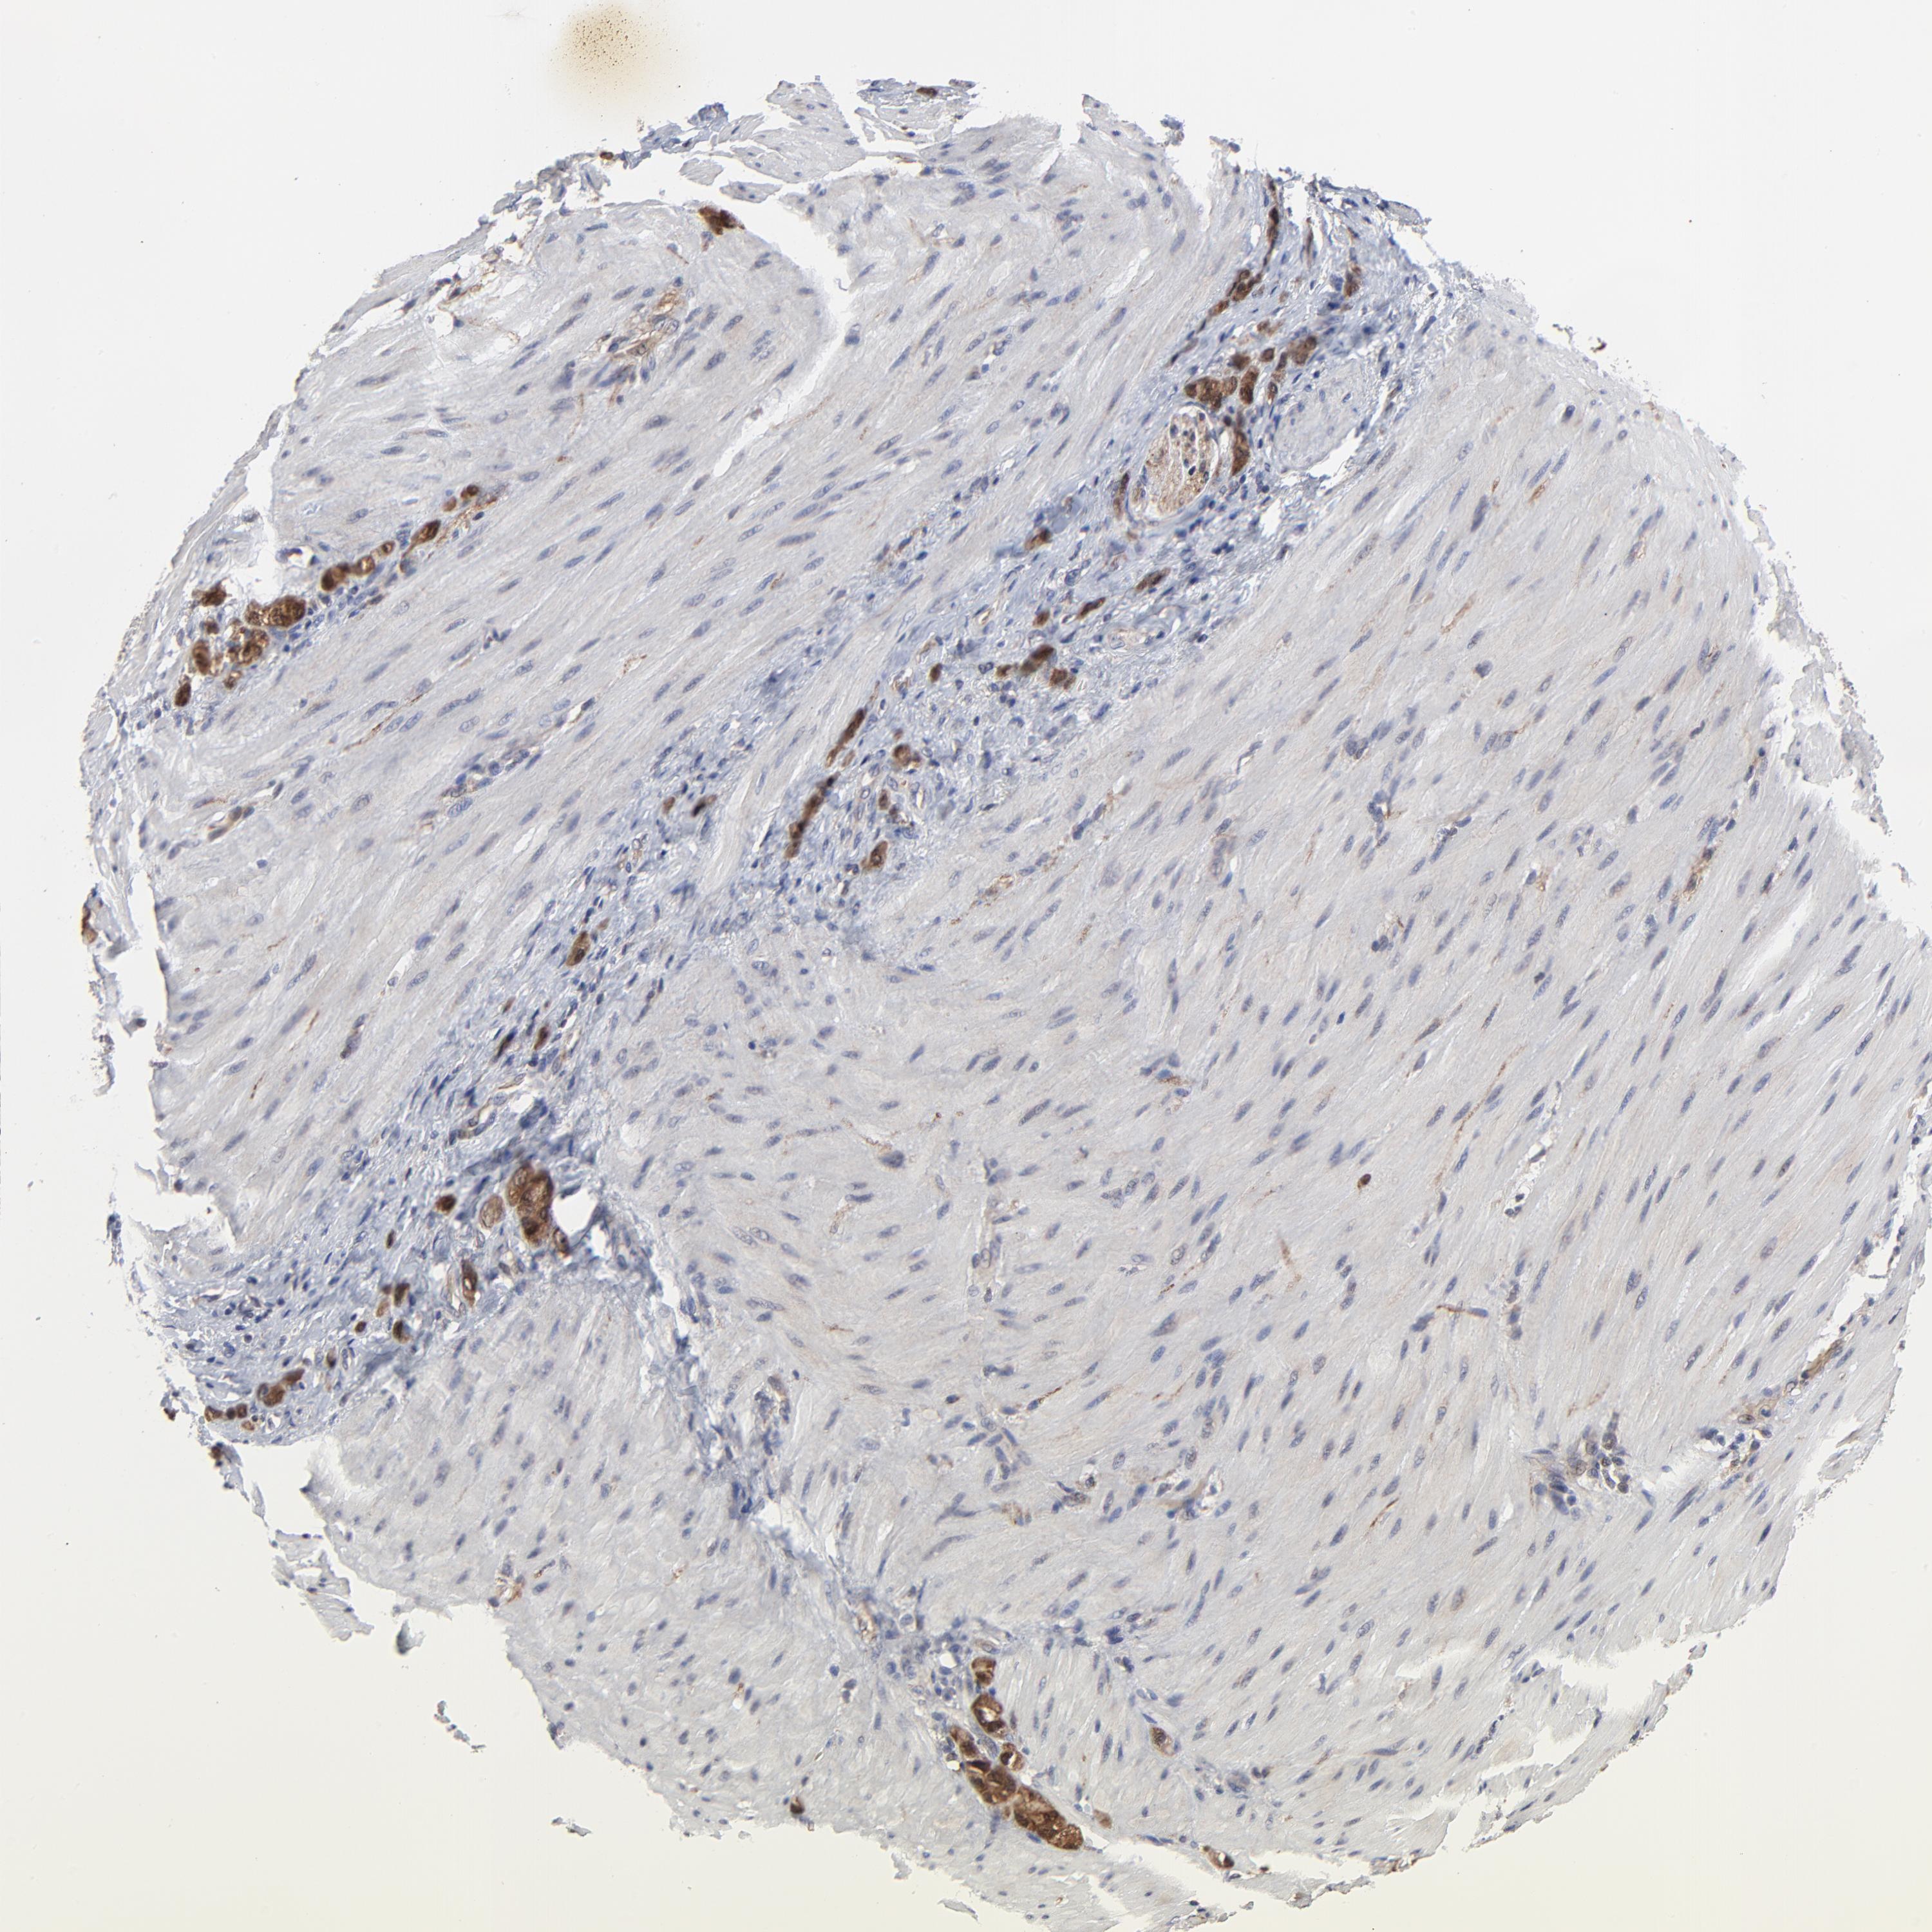

STOMACH CANCER - Protein expressioni

A mouse-over function shows sample information and annotation data. Click on an image to view it in a full screen mode. Samples can be filtered based on level of antibody staining by selecting one or several of the following categories: high, medium, low and not detected. The assay and annotation is described here.

Note that samples used for immunohistochemistry by the Human Protein Atlas do not correspond to samples in the TCGA dataset.

Antibody stainingi

Antibody staining in the annotated cell types in the current human tissue is reported as not detected, low, medium, or high, based on conventional immunohistochemistry profiling in selected tissues. This score is based on the combination of the staining intensity and fraction of stained cells.

Each image is clickable and will lead to virtual microscopy that enables deeper exploration of all samples and also displays staining intensity scores, fraction scores and subcellular localization as well as patient and tissue information for each sample.

Antibody HPA002861

Staining

High

Medium

Low

Not detected

Intensity

Strong

Moderate

Weak

Negative

Quantity

>75%

75%-25%

<25%

None

Location

Nuclear

Cytoplasmic/membranous

Cytoplasmic/membranous,nuclear

Adenocarcinoma, NOS

Adenocarcinoma, High grade